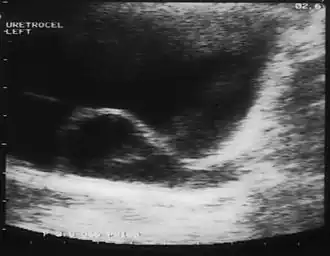

Уретероцеле — сужение устья мочеточника, приводящее к образованию шаровидного и кистовидного выпячивания (грыжеподобного) внутрипузырного отдела мочеточника, состоящего из двух слоёв слизистой оболочки — внутри мочеточника и снаружи мочевого пузыря, ввиду чего происходит нарушение оттока мочи и возникновение уретрогидронефротической трансформации и хронического пиелонефрита[2].

Диагностика сводится к экскреторной урографии (внутривенное введение рентгеноконтрастного вещества), УЗИ почек или мочевого пузыря, цистография, цистоскопия[5].